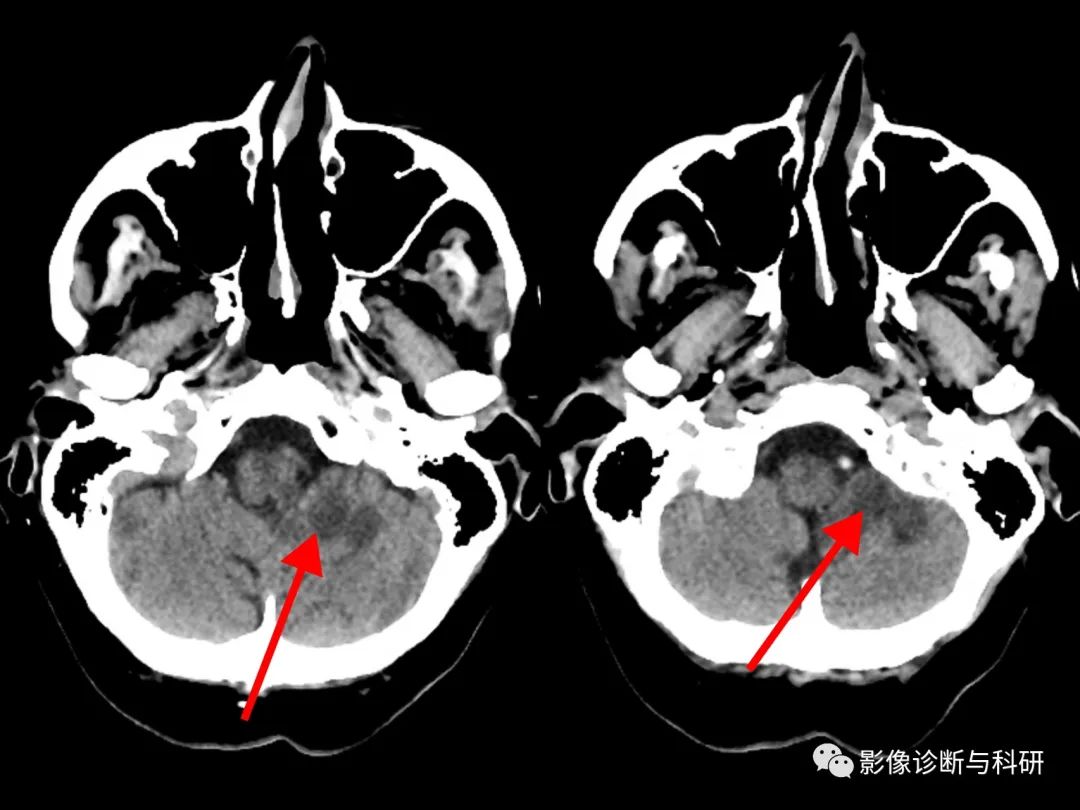

53 岁,男子,眩晕、恶心和呕吐。MR提示小脑后下动脉 (PICA) 分布区高信号,邻近的脑干和第四脑室受到压迫。